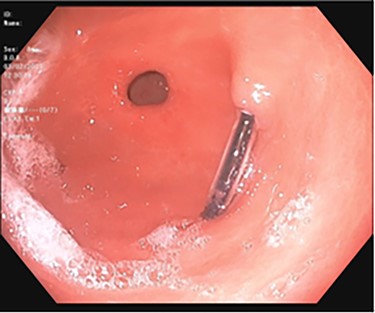

A 43-year-old incarcerated woman with borderline personality disorder and a long history of swallowing various foreign objects in periods of stress presented to the emergency department after swallowing a cup of bleach. Her surgical history was significant for multiple celiotomies for retrievals of purposefully ingested foreign bodies. During evaluation, she also admitted to swallowing an ink pen 3 weeks prior to swallowing the bleach for which she did not seek medical evaluation. She reported no food intolerance or changes in bowel function secondary to swallowing these objects. She presented with mild abdominal pain and cramping, and her vital signs and laboratory investigations were all within normal limits. Her abdominal exam was notable for mild tenderness to palpation diffusely. Computed tomography (CT) of the abdomen (Fig. 4) showed a linear foreign body in the distal gastric antrum penetrating the inferior wall and extending into the adjacent peritoneal fat. No free air or free fluid was appreciated. Initial esophagogastroduodenoscopy (EGD) was significant for mild erythema and edema to the esophageal and duodenal mucosa as a result of the caustic ingestion, and the pen was found to be deeply perforating the stomach antral wall with no associated ulcer or edema (Fig. 1). The depth at which the foreign body was lodged was uncertain, so there was concern for organ involvement outside of the gastric wall. Repeat EGD was done to assess for manifestations of esophageal, gastric or duodenal injuries from her caustic ingestion, and it revealed normal gastric mucosa (Fig. 2). A joint case was planned with the gastroenterology service for endoscopic foreign body retrieval, possible laparoscopic retrieval and gastric repair and possible open retrieval and gastric repair. The patient was taken to the operating room for the third EGD, which revealed spontaneous migration of the foreign body from the perforation site into the lumen of the gastric body (Fig. 3a). Additionally, there was spontaneous closure of the site of previous perforation (Fig. 3b and c). The ink pen was easily removed transorally using an endoscopic snare, and no further surgical intervention was required. After the procedure, the patient reported complete resolution of her abdominal pain and was able to tolerate a regular diet without problems.

EGD on initial presentation; gastric antrum with foreign body perforating through the gastric wall.